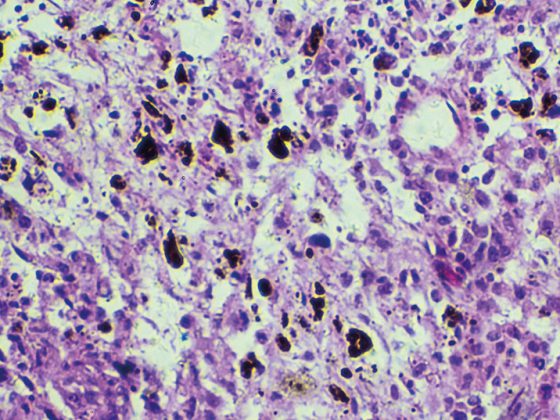

Komplizierte Nierenzysten